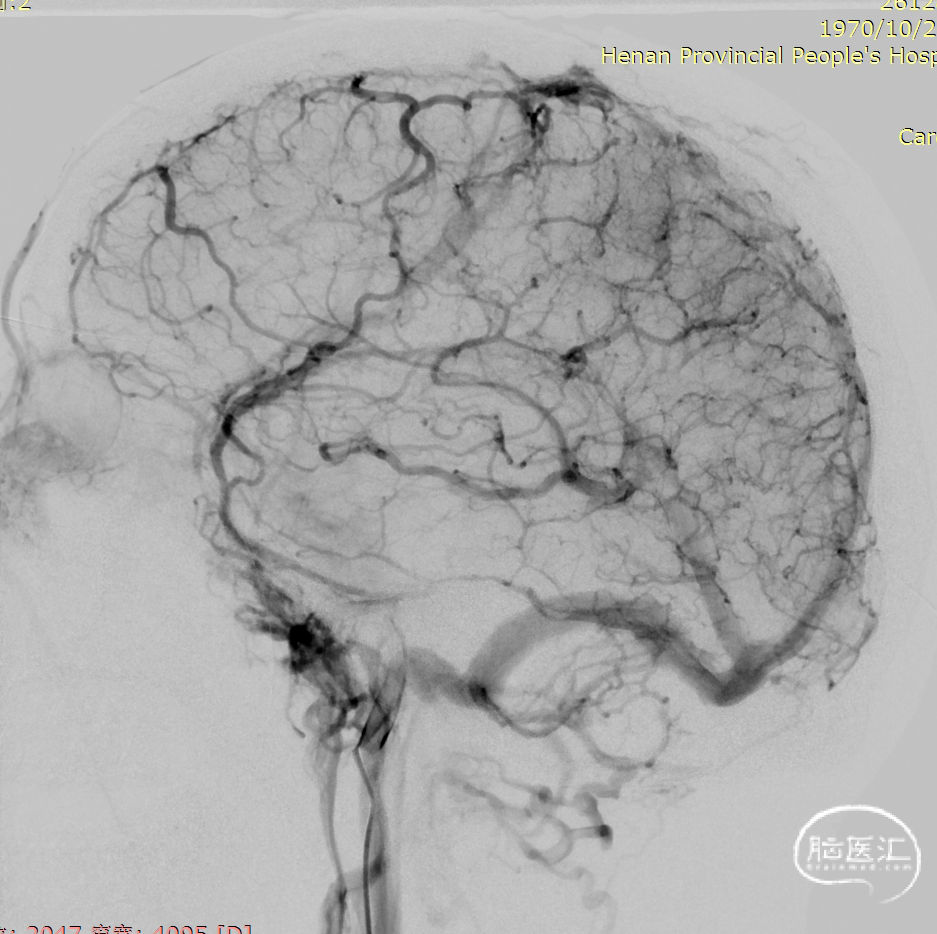

术前DSA静脉期可见上矢状窦及右侧横乙窦充盈缺损。

术后造影显示上矢状窦较前明显改善。

术前上矢状窦闭塞

术后上矢状窦再通